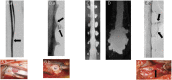

Results: Among 398 patients with SIH and extradural CSF on spinal imaging, multiplicity of CSF leaks was observed in none of 291 patients with type 1a ventral leaks and in 4 (6.2%) of 65 patients with type 1b (postero-) lateral leaks. Among 97 patients with SIH from spinal CSF-venous fistulas (type 3 leaks) who did not have extradural CSF on spinal imaging, 9 patients (9.3%) had multiple fistulas (p < 0.0001 for comparison between groups). Type 3 and type 1a or 1b CSF leaks coexisted in an additional 5 patients.